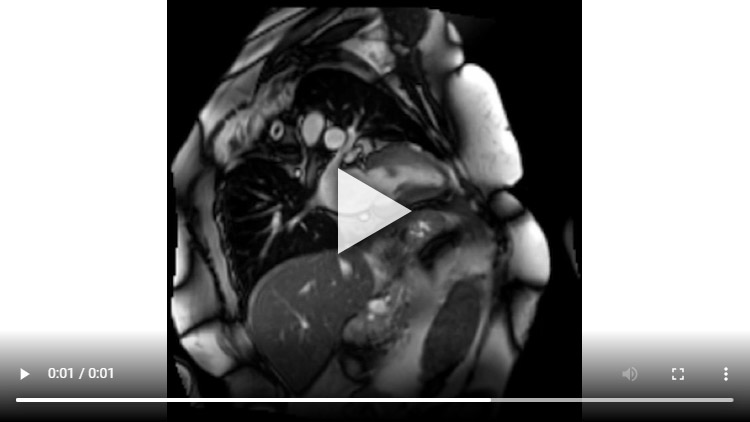

Figure 6 : Séquence de perfusion premier-passage au stress

Coupes petit-axe basal (A), médian (B) et apical (C)

On peut noter deux types d’hypoperfusion distinctes (flèches rouges) :

- une hypoperfusion sous-endocardique inféro-latérale correspondante à la séquelle d’IDM inféro-latéral déjà connue en 2011

- une hypoperfusion sous-endocardique de 2-3 segments sur 17 en antéro-basal et antérolatéral correpondant à une ichémie inductible.

Pour rappel : la définition d’une ischémie myocardique inductible est la présence d’une hypoperfusion sous-endocardique au stress SANS présence d’un rehaussement tardif dans la même zone.